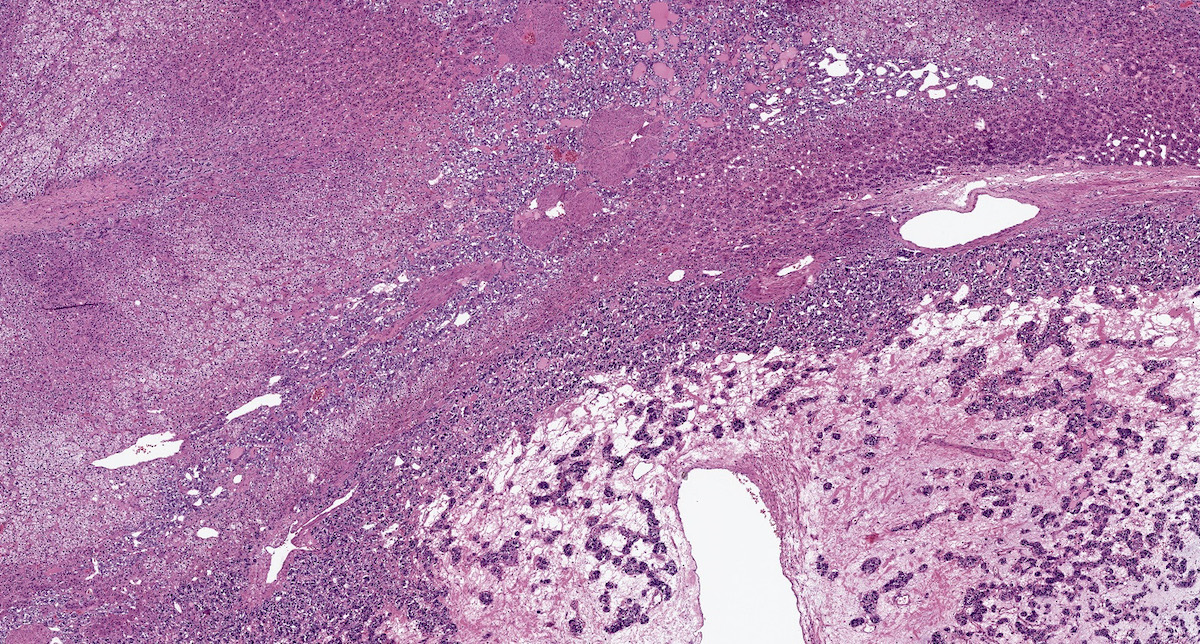

Microscopic (histologic) description

- Prevailing histologic pattern: epithelioid chief cells arranged in distinctive clusters / nests (zellballen pattern), separated by prominent fibrovascular stroma (J Clin Med 2018;7:280)

- Trabecular pattern: ribbons or cords of epithelioid cells divided by fibrous bands

- Other patterns: pseudorosette, angioma-like, spindled and sclerosing

- May have dysmorphic vessels, melanin-like pigment (neuromelanin) (pigmented paraganglioma), amyloid, abundant stroma and osseous metaplasia (Diagn Pathol 2012;7:77, Hum Pathol 1992;23:33)

- Necrosis is unusual except in patients who have undergone preoperative tumor embolization

- Special histopathologic features usually related to genetic syndromes:

- VHL syndrome: prominent stromal edema, clear cytoplasm and lipid degeneration (Am J Surg Pathol 1987;11:480)

- SDHx related syndrome: granular eosinophilic cytoplasm (Am J Surg Pathol 2020;44:422)

- MEN2 syndrome: unilateral or bilateral adrenal medullary hyperplasia (Neoplasia 2014;16:868)

Microscopic (histologic) images

Contributed by Luvy Delfin, M.D. and Sylvia L. Asa, M.D., Ph.D.